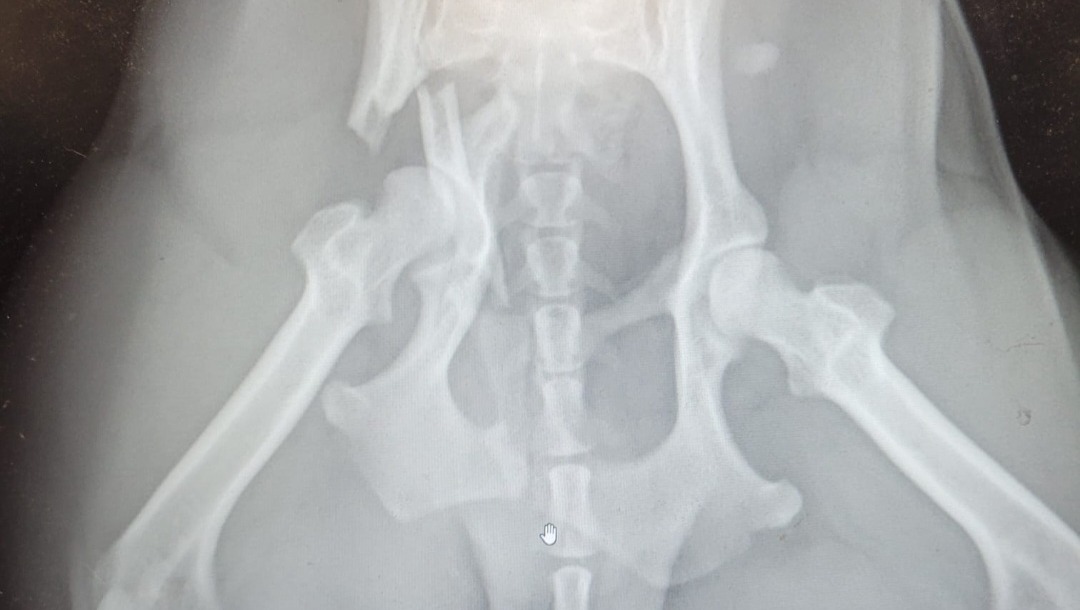

Hi My name is Samantha Hernandez I'm fundraising for funds to cover our family pet Canela's Surgery and recovery. On March 17th at 5 a.m Canela got hit by a car. She survived but sadly suffered a head injury and multiple traumatic pelvic fractures. She will need invasive surgery and therapy after for recovery. Canela is 1 and half years old and has loving and strong spirit, we are hopeful and reassured she can make a great recovery but it will be a long and expensive one. I am hoping who ever this fundraiser reaches that you can make a donation, share or even send a prayer. A donation of any amount is appreciated. Canela is an important part of our family and we appreciate you taking your time out to share this fundraiser,any donations along with prayers. We beg that you share this fundraiser to who ever you can so we can get the proper care Canela needs PLEASE! She is soooo very important to us and we want to make sure she gets the best and proper care needed medically and while recovering. Thank you and may God bless you all.